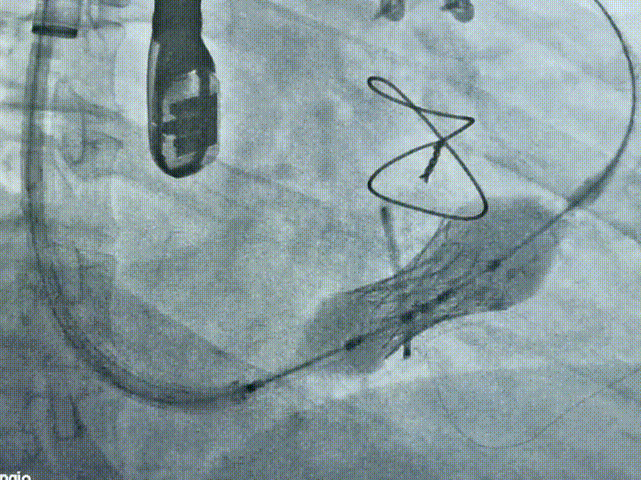

术中释放过程

术后造影